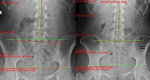

[Purpose] To present the successful structural improvement in cervical lordosis in a patient suffering from cervicogenic headache having cervical kyphosis. [Participant and Methods] A 26 year old female presented with the primary complaint of headache. Radiography demonstrated a cervical kyphosis. Chiropractic BioPhysics® methods were used to restore the cervical spine alignment. Twenty-five treatments were given over 8 weeks. A 2.5 year follow-up was also reported. [Results] Radiography showed a dramatic increase in cervical lordosis following initial treatment. The patient also reported substantial reductions in headache frequency and severity as well as other bodily improvements, reduced disability and improved quality of life. The long-term follow-up showed a maintenance of lordosis correction and patient wellness. [Conclusion] A cervical kyphosis was reversed back to a normal lordosis in 8 weeks and coincided with dramatic resolution of cervicogenic headache in a young female. The cervical lordosis may be a key biomechanical biomarker in cervicogenic headache.